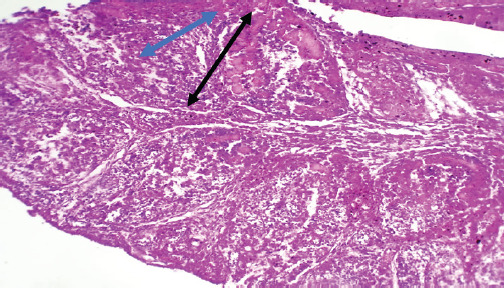

目的:从疑似感染的肉鸡养殖场中鉴定和检测重组传染性法氏囊病病毒(IBDV)。材料与方法:取肉仔鸡脾、法氏囊72份标本。在用于典型的PCR分子研究之前,对组织进行组织学检查。结果:该菌株被命名为IBDV ASPVB。基于PCR、测序和部分a段和b段的系统发育分析,伊拉克的IBDV ASPVB菌株被鉴定为一种新的重组菌株。相比之下,片段B来自其他田间重组菌株。感染该菌株可能导致轻微的临床症状,但对淋巴器官造成严重损害,导致免疫反应受损。结论:由于持续的进化,本研究表明伊拉克的IBDV表现出广泛的组织学、遗传和表型变异;据我们所知,这是伊拉克首次报道重组IBDV。

Materials and methods: The broiler yielded 72 samples, including the spleen and bursa of Fabricius. The tissues underwent histological examination before being used in a typical PCR molecular investigation.

Results: The strain was subsequently termed IBDV ASPVB. The IBDV ASPVB strain in Iraq has been identified as a novel reassortant strain based on the results of PCR, sequencing, and phylogenetic analysis of partial segments A and B. Segment A of this strain is derived from the highly pathogenic IBDV strain. In contrast, segment B is derived from other field reassortant strains. Infection with this strain might result in minor clinical symptoms but substantial damage to lymphoid organs, leading to compromised immunological responses.